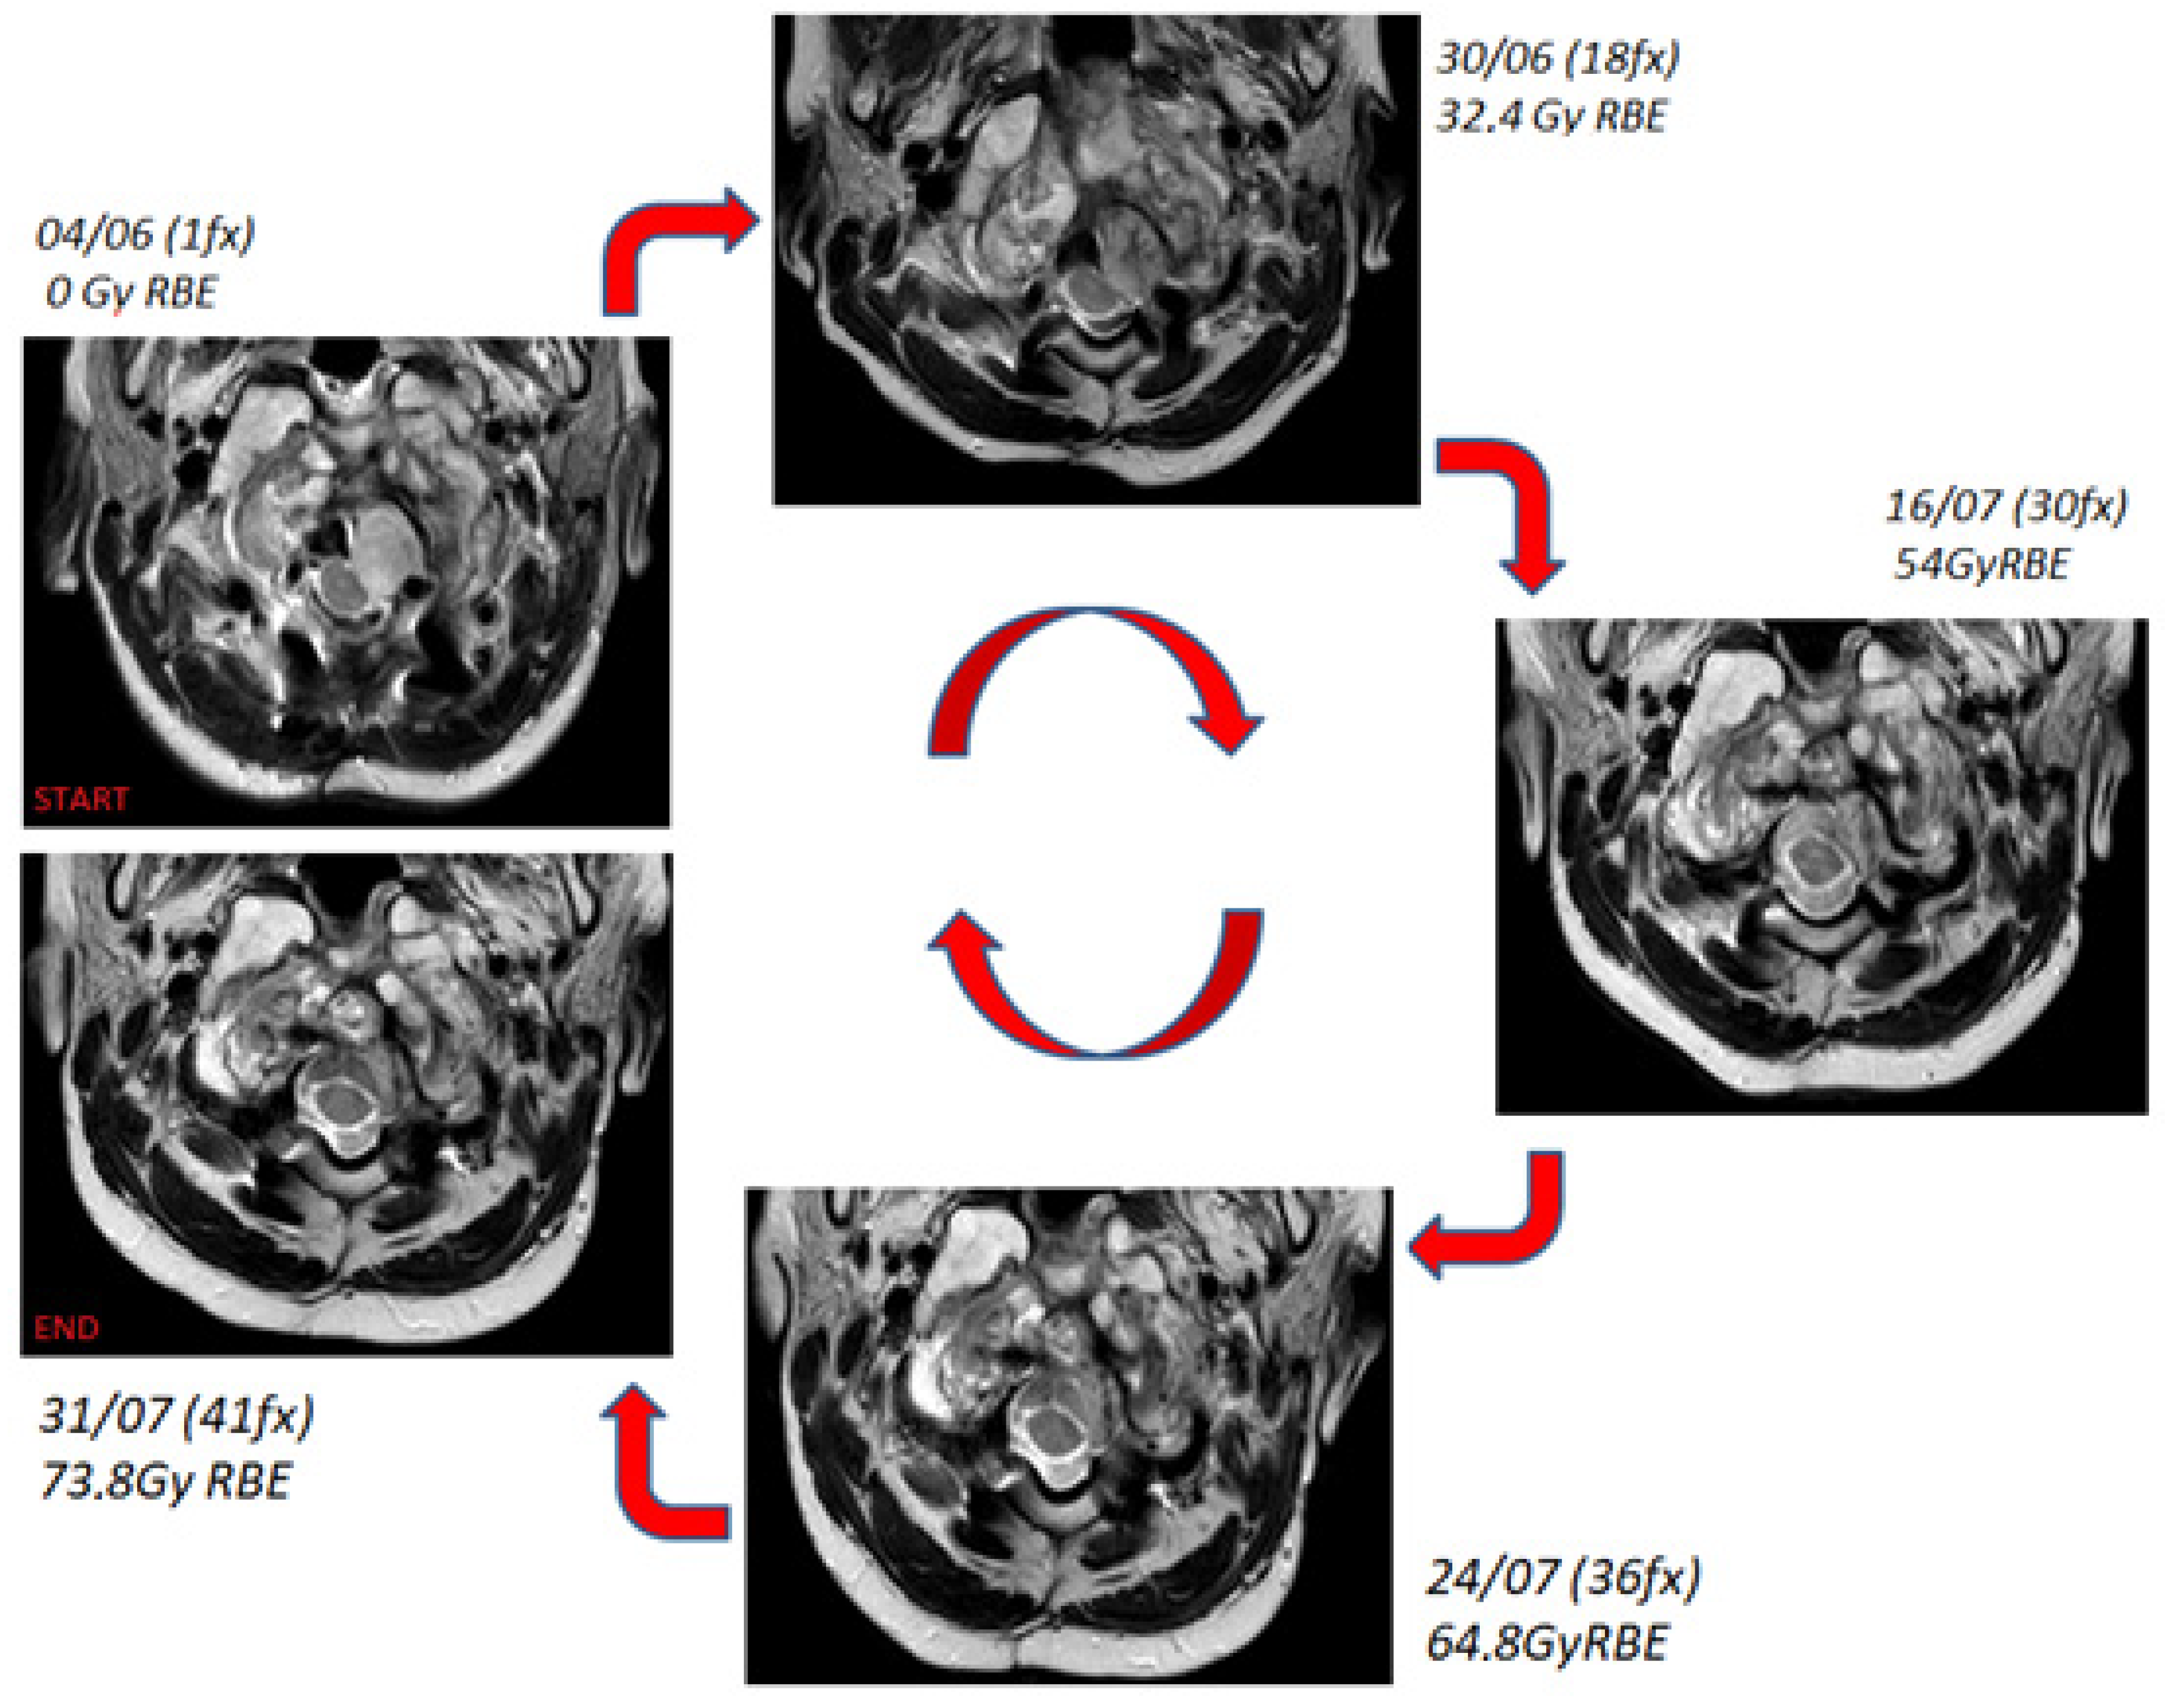

A computed tomography (CT) scan of the patient in supine position was acquired. To guarantee the immobilization and reproducibility of the patient position on the treatment couch, a thermoplastic mask coupled with a customized cushion made of a dedicated foam-like material was used. The CT scan and the pre-treatment MRI images were registered to help the clinician to identify the structures of interest. The clinician used the CT images to define the target volume and OARs to be spared. The treatment plan was then prepared using a commercial treatment planning system (Elekta XIO) equipped with a pencil beam dose calculation algorithm. A 3-field (1 posterior and 2 anterior-oblique) plan was created using a single-field-optimization technique [14]. The total prescription dose for the target was 73.8 GyRBE, delivered in 41 fractions (1.8 GyRBE per fraction, 5 fractions a week), while the main constraints (expressed as allowed dose to 1% of the volume) were set for the brainstem and spinal cord at 54 GyRBE and 50 GyRBE, respectively. The treatment was delivered in a proton therapy gantry room featuring a pencil beam active scanning technique. The Figure 3 shows the planned dose distributions on the CT scan.

The following contours are reported: planning target volume 0–54 GyRBE (blue), planning target volume 54–73.4 GyRBE (red), nodule component (green), brainstem (purple), and spinal cord (yellow).

Figure 3. Treatment planning: proton dose distributions in coronal, axial and sagittal views.